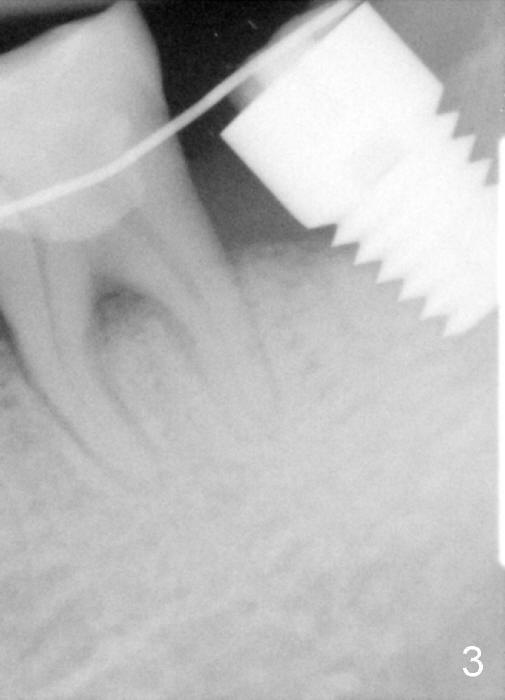

The soft tissue heals around the implant 1 months postop (Fig.1), but the implant (7x11 mm) is unstable. It should have been placed 2 mm deeper (Fig.2).  It is splinted for the neighboring tooth (Fig.3).  When the splint is removed 4 months later, the implant remains mobile.  It is removed with infiltration anesthesia.  The osteotomy is deepened by approximately 2 mm.  A 7x14 mm tap is inserted with stability (Fig.4); there is apical space to be engaged further (arrowheads).  A 7x14 mm implant is placed with insertion torque > 60 Ncm (Fig.5 I); an abutment (A) placed to keep perio dressing in place.